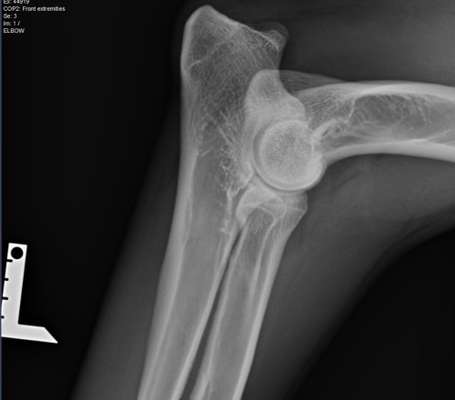

Elle links

Hab Röntgen Bilder für euch. Lagerung nicht perfekt und bin gespannt was der Doktor zum LÜW sagt...

Lendenübergangswirbel

Sieht irgendwie "schief" aus.🤔

Was sagt der Tierarzt zu der hüfte da sind die Pfannen nicht weit genug ausgebildet das ist jetzt nicht so tragisch wäre aber sehr wahrscheinlich hd nochzugelassen wenn überhaupt

Ja 16/17und 17 sehen auffällig aus kann aber auch von der schlechten lagerung sein